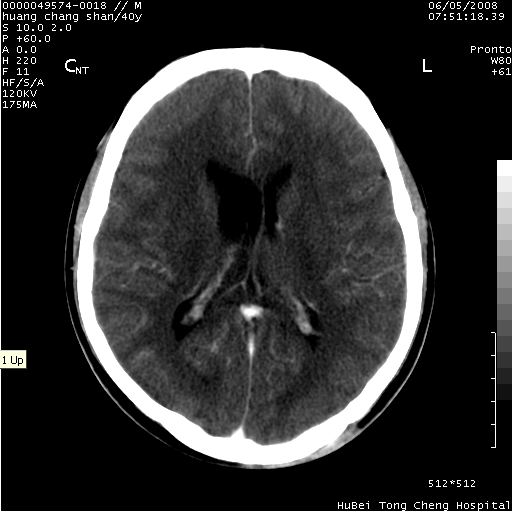

患者 m,40y。头痛,视力模糊,多饮多尿,性欲减退半年余。

行ct平扫+增强,图象如下:

结合临床考虑鞍上生殖细胞瘤可能性大于脑膜瘤(增强未见脑膜围征),建议结合冠状位扫描看病灶起源及垂体窝、鞍底情况。垂体窝内未见明显软组织密度影,垂体窝未见扩大,暂不考虑垂体瘤;病灶较大,未见囊变及钙化,颅咽管瘤不支持。期待结果!

1、头痛,视力模糊,多饮多尿,性欲减退半年余,提示:肿瘤为功能性肿瘤。

2、ct表现:肿瘤呈类圆形,均匀略高密度,无囊变,无钙化。侧脑室有扩大。

3、首先考虑:功能性垂体大腺瘤。

4、鉴别诊断:脑膜瘤,瘤体内点状钙化最具特征性,常位于鞍结节。颅咽管瘤,蛋壳样钙化,常有囊变。动脉瘤,位于鞍旁,强化与动脉一致。有时尚需与发生于鞍区的生殖细胞瘤鉴别,生殖细胞瘤钙化亦较常见。

5、友情提示:下回发现鞍区占位性病变,最好加扫冠状位,了解肿瘤与蝶鞍的关系及蝶鞍骨质的改变。